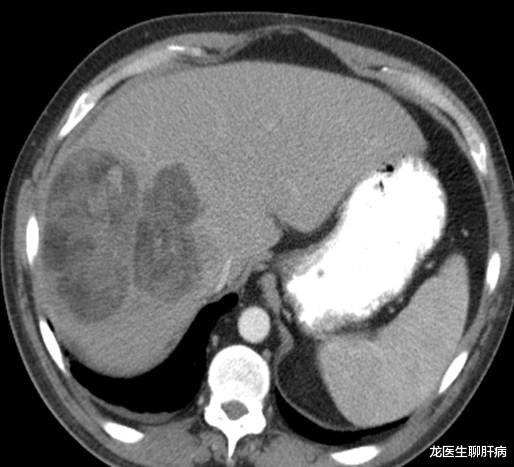

影像学检查包括增强CT、超声和磁共振 , 对于难以确诊的病例 , 肝血管造影可能有助于诊断 。 如果影像学有特征性的表现 , 且抱伴有甲胎蛋白升高 , 诊断可以明确 。 必要的时候 , 可以在超声或CT引导下做肝活检 , 以进一步明确诊断 。